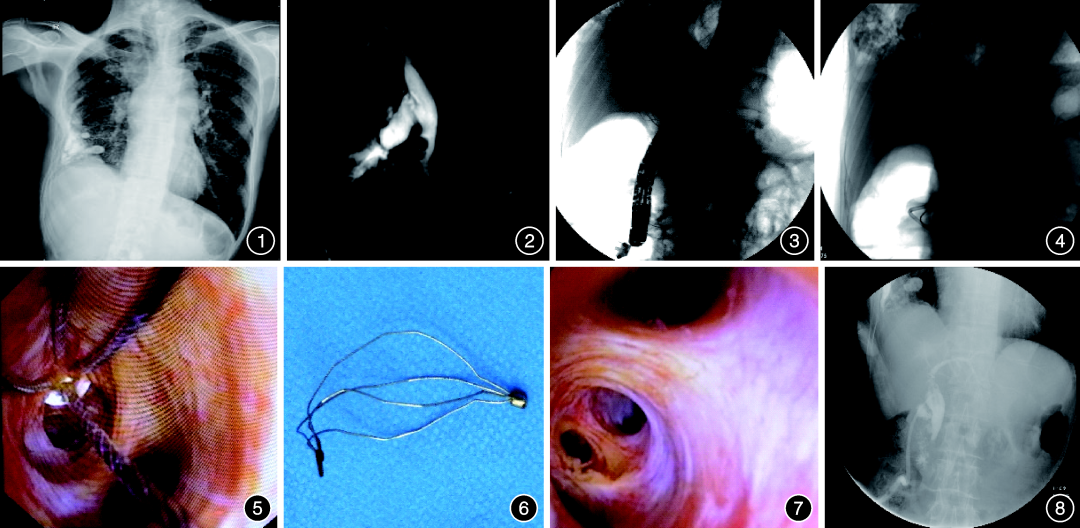

ERCP过程中胆管插管造影显示胆总管显著扩张约13mm,其内可见2枚充盈缺损,最大直径约8mm,乳头中切开,少量渗血。取石网篮套取结石,取出多个碎块,球囊清理出泥沙样结石。造影显示仍有充盈缺损,网篮再次取石时发生嵌顿,X线下观察网篮头端位于肝右叶(图3),可张开和回收,但体外牵拉时患者剧烈疼痛,反复尝试无法取出而终止操作。留置鼻胆管于右肝管分支胆管(图4)。急诊行腹腔镜联合胆道镜下胆总管探查术。术前诊断:1.胆总管结石;2.胆道异物(取石网篮嵌顿);3.胆囊炎。术中胆道镜探查见取石网篮嵌顿于右肝管三级胆管汇合处,其内无结石和组织(图5),并见胆总管残余结石,左右肝管、肝总管未见结石。剪断网篮后将其和导管分别经腹壁和口腔取出,嵌顿处黏膜有损伤(图6、7)。清理结石、冲洗胆道,胆总管内置22号T管引流。于胆囊床置22号腹腔引流管引流。术后给予抗炎及保肝支持治疗,T管引流通畅,无发热等情况。术后1周复查肝功能:总胆红素46.7μmol/L,直接胆红素30.7μmol/L,谷丙转氨酶46U/L,白蛋白28.6g/L,谷氨酰转肽酶132U/L,淀粉酶132U/L。予带T管出院。术后8周复查肝功能正常、T管造影未见结石残余(图8)后拔管,患者康复良好。

1 胸部正位片示右侧胸膜钙化灶并粘连,左肺代偿性肺气肿  图2 磁共振胰胆管成像示胆总管中下段多发结石  3 经内镜逆行胰胆管造影术X线下显示网篮嵌顿于肝右叶  4 留置鼻胆管于右肝管分支胆管  5 术中胆道镜探查可见取石网篮嵌顿于右肝管三级胆管汇合处  6 切断后取出的网篮  7 嵌顿处损伤的胆管内膜  8 T管造影未见结石残余